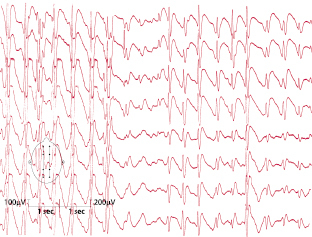

Dieses Syndrom ist gekennzeichnet durch das Auftreten unterschiedlicher Anfallsformen (tonisch, tonisch-klonisch, tonisch-astatisch, myoklonisch-astatisch, Nick- und fokale Anfälle, atypische Absencen) zwischen dem 2. und 7. Lebensjahr. Bei ca. 20% der Fälle geht ein West-Syndrom voraus. Die Prognose ist sehr ungünstig. Neben Therapieresistenz findet sich häufig eine deutliche Retardierung. Das EEG ist charakterisiert durch meist generalisierte, frontal betonte, langsame 2–2,5/s „sharp-“ bzw. „spike-slow waves“: Spike-wave-Variant-Muster (Abb. 7.5).

Leitsymptom sind myoklonische und atonisch-astatische Anfälle. Heftige Anfälle mit plötzlichem Hinstürzen sind nicht selten. Prädilektionsalter ist das 1.–5. Lebensjahr. Die Behandlung gestaltet sich meist problematisch. Im EEG zeigen sich kurze generalisierte Paroxysmen unregelmäßiger 2–3/s „spike-waves“ (Abb. 7.6).